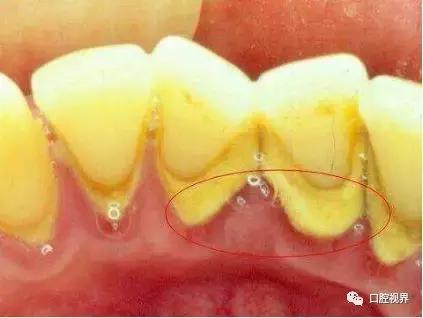

(牙石)

⭐症状:口臭,刷牙出血,发现牙石、要求洗牙、牙龈红肿疼痛。

就诊科室:牙周科/牙周治疗中心,口腔内科

简介:牙周病是指发生在牙支持组织(牙周组织)的疾病,包括仅累及牙龈组织的牙龈病和波及深层牙周组织(牙周膜、牙槽骨、牙骨质)的牙周炎两大类。牙周疾病是常见的口腔疾病,是引起成年人牙齿丧失的主要原因之一,也是危害人类牙齿和全身健康的主要口腔疾病。